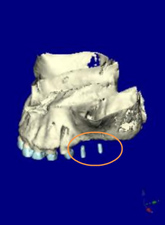

CTデータより3D画像を構築

左上に2本のインプラントを計画

上顎咬合面観